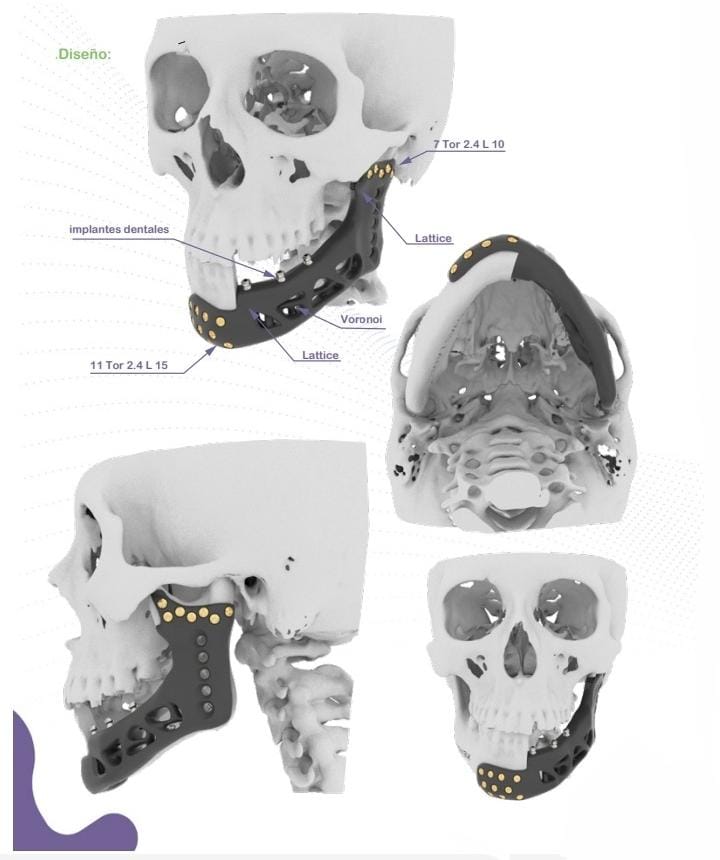

Esta tecnología no solo se aplica en cirugía buco máxilo cráneo facial, sino también en cirugía ortopédica.

Diseño a medida

Cada implante se fabrica adaptado a la anatomía específica del paciente, mejorando la precisión y el resultado clínico.

Captura y Modelado 3D

La reconstrucción anatómica se realiza a partir de imágenes obtenidas mediante técnicas de diagnóstico como Tomografía Axial Computada (TAC) o Resonancia Magnética (MRI). Estas imágenes son procesadas con software especializado para modelar en tres dimensiones cualquier región anatómica, incluso con patologías complejas.

Inclusión de Implantes

En el modelado digital 3D se pueden incluir implantes ortopédicos como placas, tornillos, mallas, prótesis y otros dispositivos, diseñados en tamaño real y en relación directa con la anatomía del paciente. Esto permite simular distintos escenarios quirúrgicos antes de la cirugía.

Ver másCirugía Maxilofacial

Implantes adaptados a la anatomía facial del paciente, planificación quirúrgica digital y reducción de tiempos en sala de operaciones.